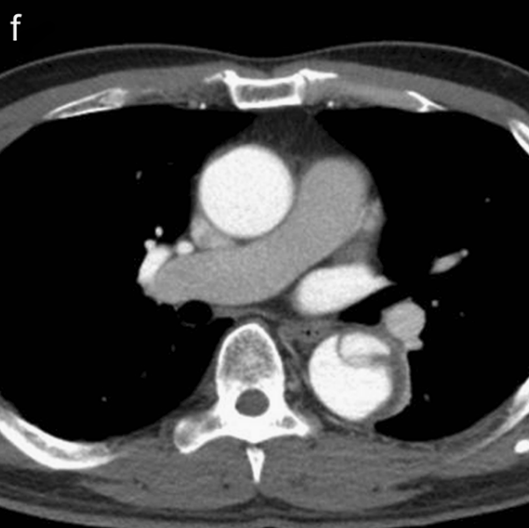

病例7

你看,我家的CT这么模糊,平扫怎么看主动脉夹层?

图18

不着急!仔细看,血管里面的“血液”居然钙化了!这叫血管钙化内移,要警惕主动脉夹层!有研究发现,血管钙化内移诊断动脉夹层的特异性高达90%。

图19

赶紧做个增强CT!主动脉裂开了!

图20